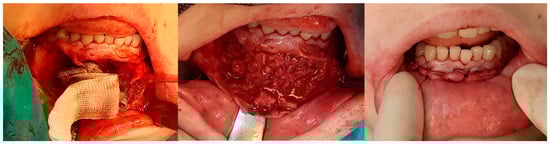

1. Introduction

3. Results

3.4. Complications During Treatment

3.5. Recurrence